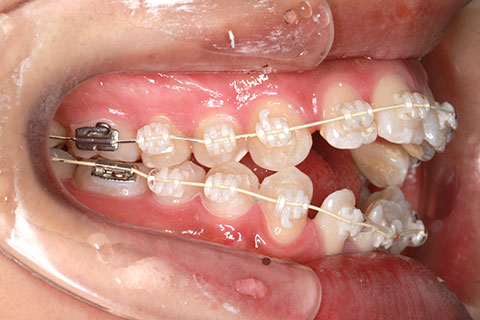

治療中

マルチブラケットを用いた矯正治療

前歯の開口を顎間ゴムにて改善